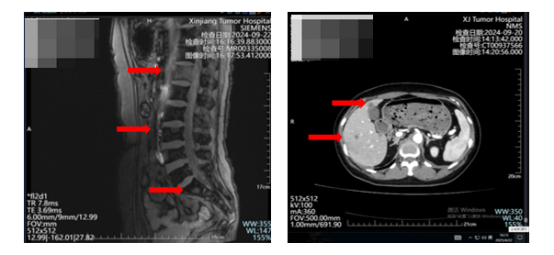

去年9月,病情平稳近一年后,复查发现肝脏又多了三个病灶,连腰椎也出现了转移。肝穿结果显示:ER(弱,25%)、PR(-)、Her-2(0)、Ki-67(60%+)。我依旧没有任何明显症状,连腹痛腰痛都没有,又是复查时“被动”发现的。

图为:2024年9月新增的肝脏和腰椎转移病灶